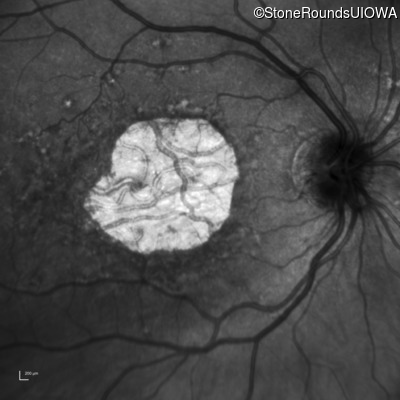

Infrared Fundus Photograph - Right - 20/125 -2

Exemplar